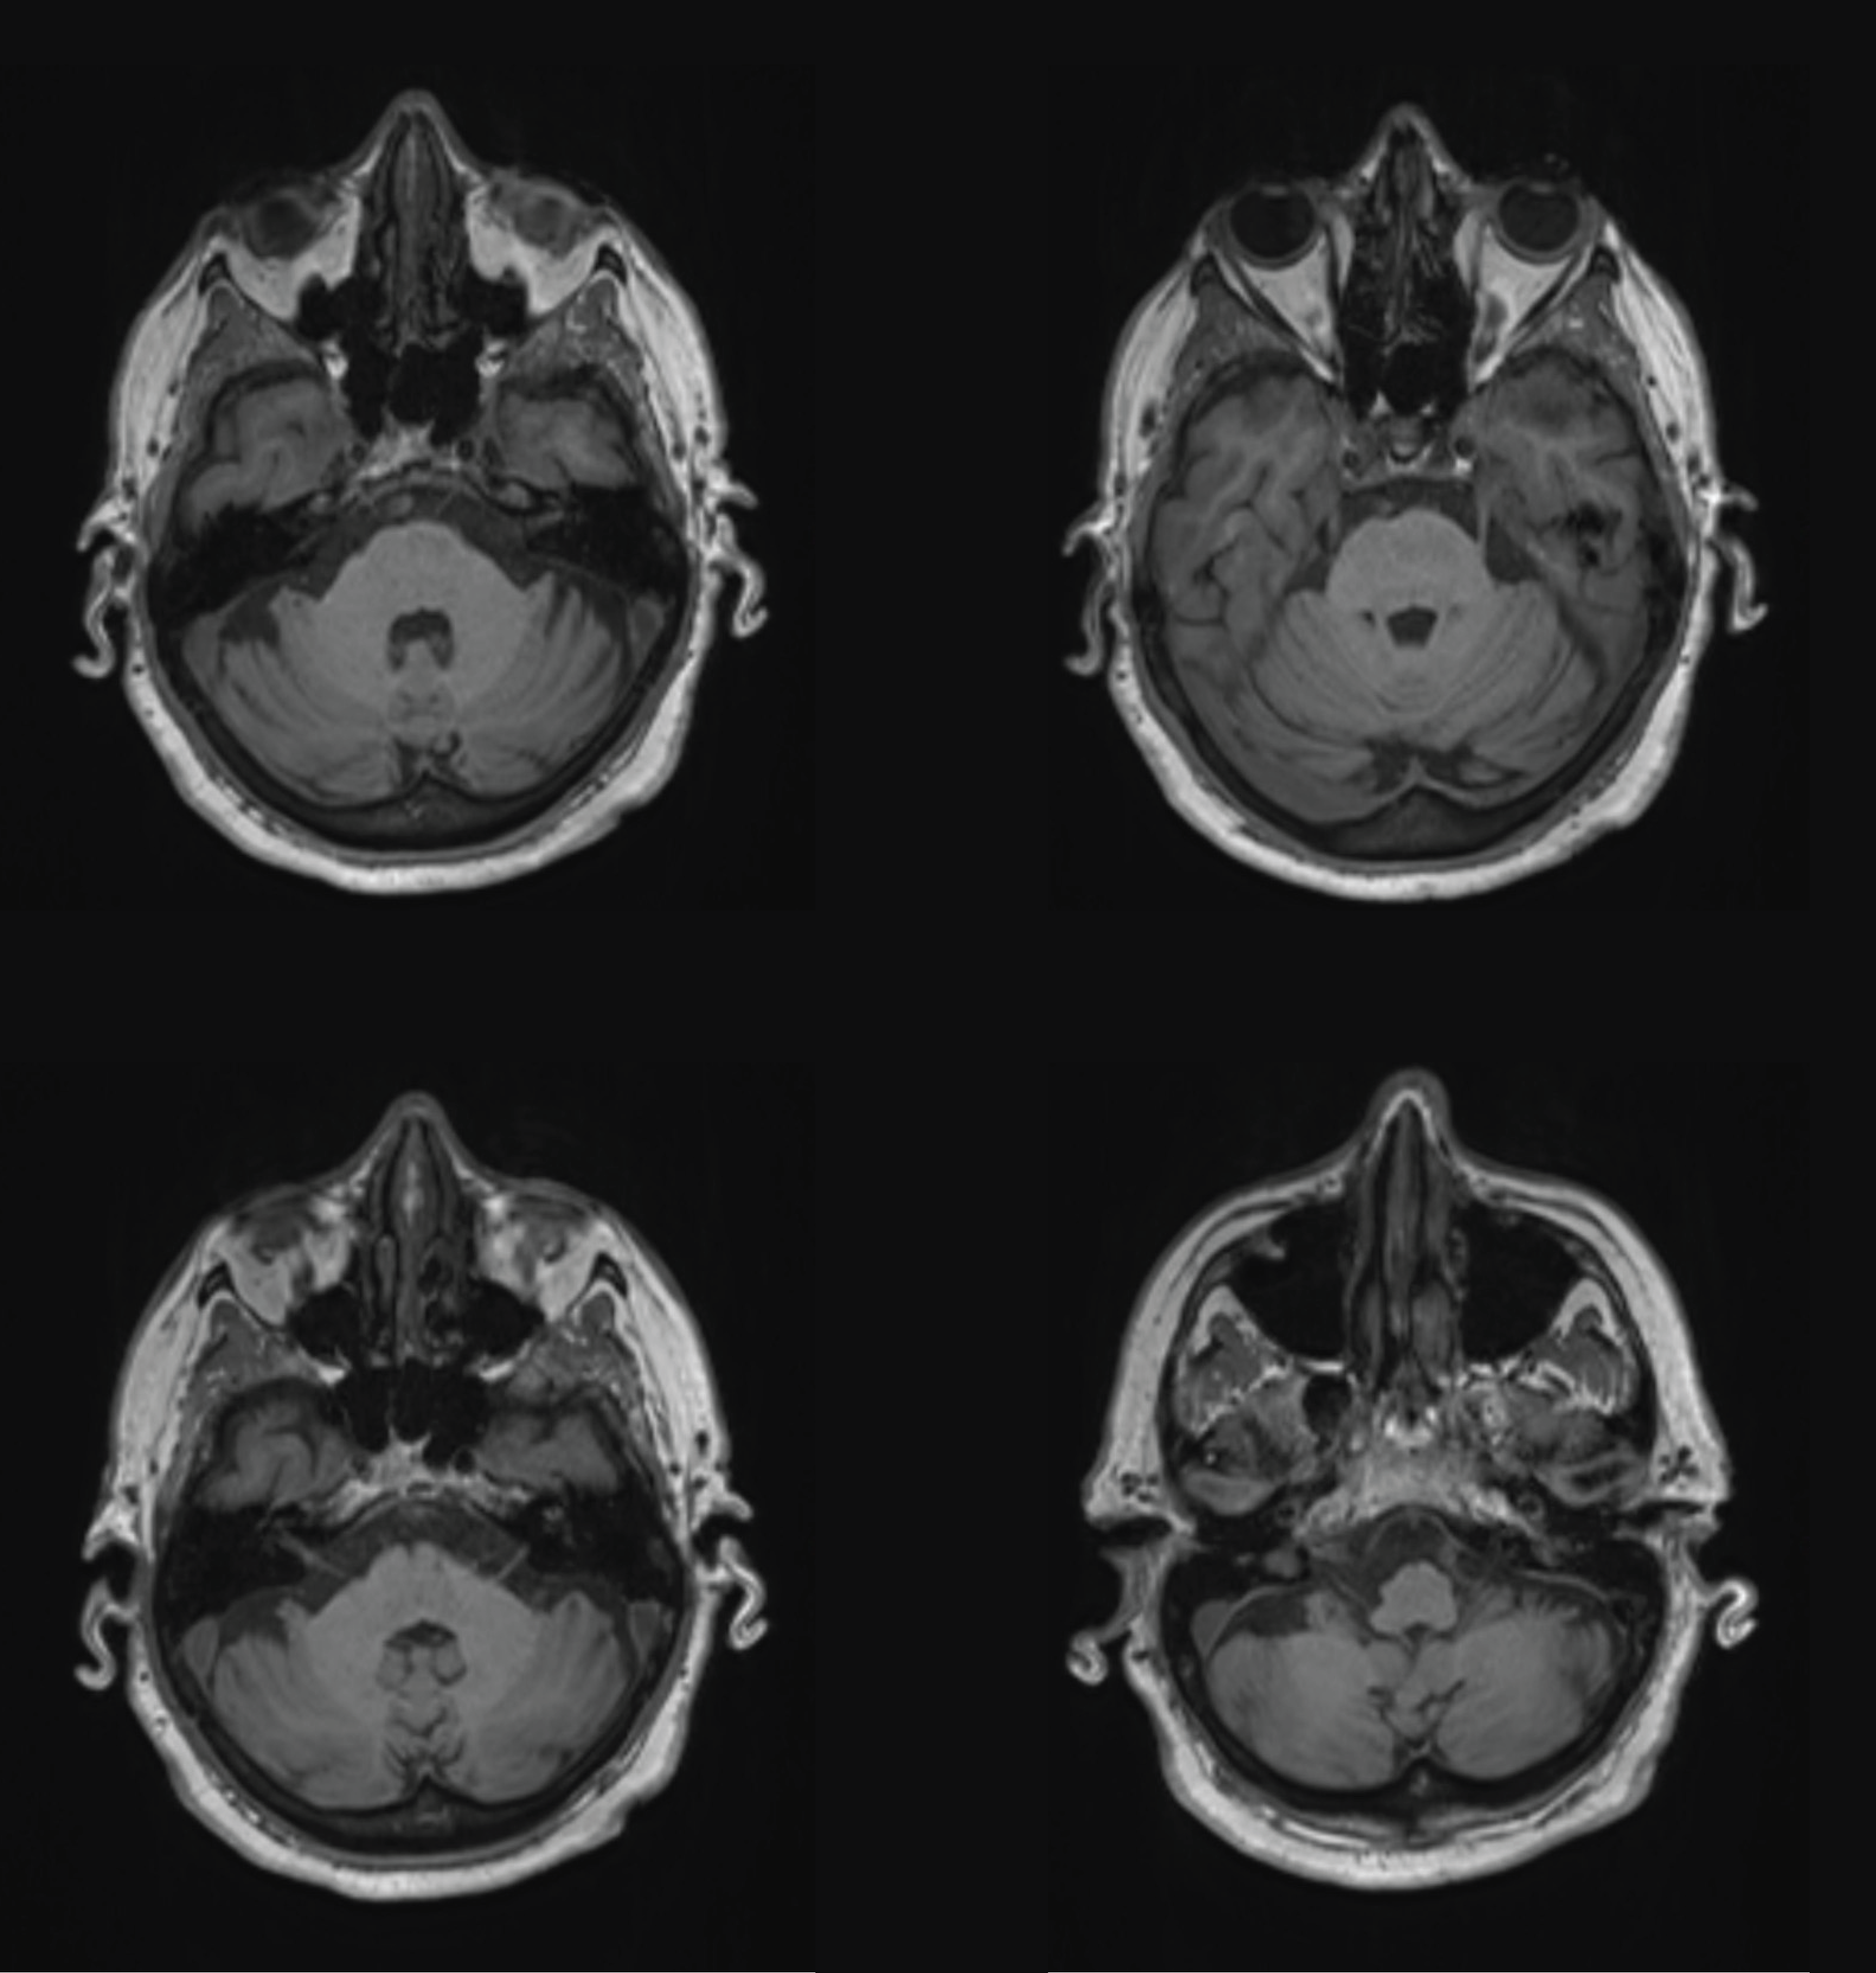

Au cours de cette unité, des travaux pratiques de neuro-anatomie sont organisés pour vous permettre d’appliquer votre savoir à l’aide de pièces anatomiques et d’images radiologiques.

Il est essentiel que vous veniez préparé.e.s à ces TP pour pouvoir en bénéficier au maximum. De plus, l’interactivité rend les TP de 4 heures moins longs et plus enrichissants. N’hésitez donc pas à participer, manipuler les pièces, poser vos questions, et participer aux dissections... À la fin de l’unité, vous devriez être à l’aise en naviguant dans le SNC et capables de mettre en lien l’anatomie des structures avec leur fonction.